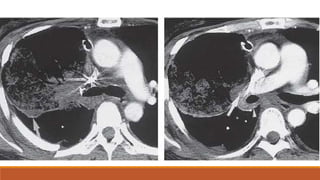

CT scan demonstrates multiple small cavities within an

area of pulmonary contusion.

Bilateral traumatic pneumatoceles. CT scan

demonstrates bilateral cysts with air-fluid levels.

CT scan demonstratesmultiple small cavities within an area of pulmonary contusion.

Bilateral traumatic pneumatoceles.CT scan demonstrates bilateral cysts with air-fluid levels.